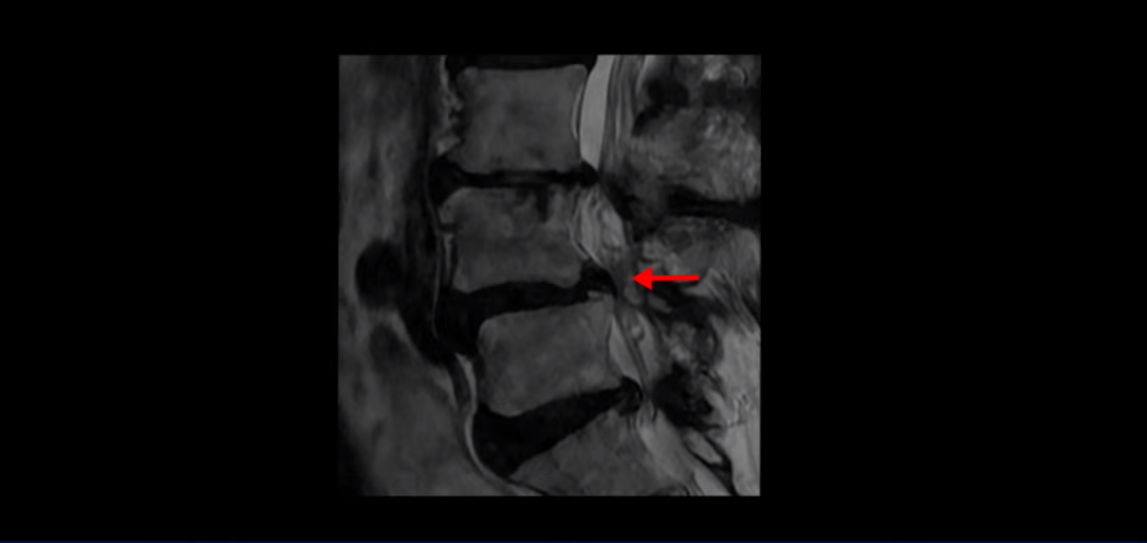

제가 먼저 이분 MRI를 보고 설명해 드린 후 어떻게 이런 분들을 수술 없이 허리 기능재활치료로 호전시킬 수 있는지 자세히 설명드리겠습니다. 이분 허리가 보시다시피 여러 마디가 퇴행되어 있고

4번 5번에는 뼈가 밀려 나간 전방전위증도 있습니다.

4번 5번 마디를 자세히 보면 심한 중심성 협착이 있어서 신경 구멍이 매우 좁아져 있습니다.

또 신경 가지가 빠져나가는 추간공도 매우 좁아져 있습니다.

그래서 양쪽 엉덩이가 아프고 다리는 발바닥까지 저리고 아프면서 발을 줄로 묶어놓은 것 같고 다리의 힘도 빠져 걷기가 어렵습니다.